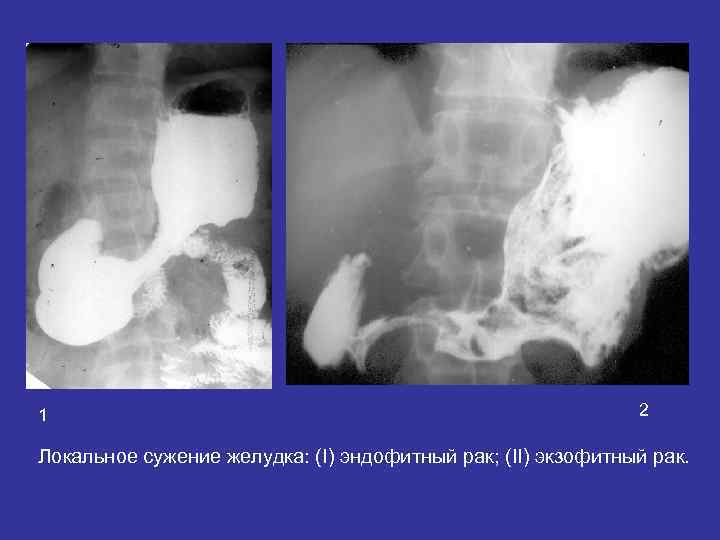

1 2 Локальное сужение желудка: (I) эндофитный рак; (II) экзофитный рак.